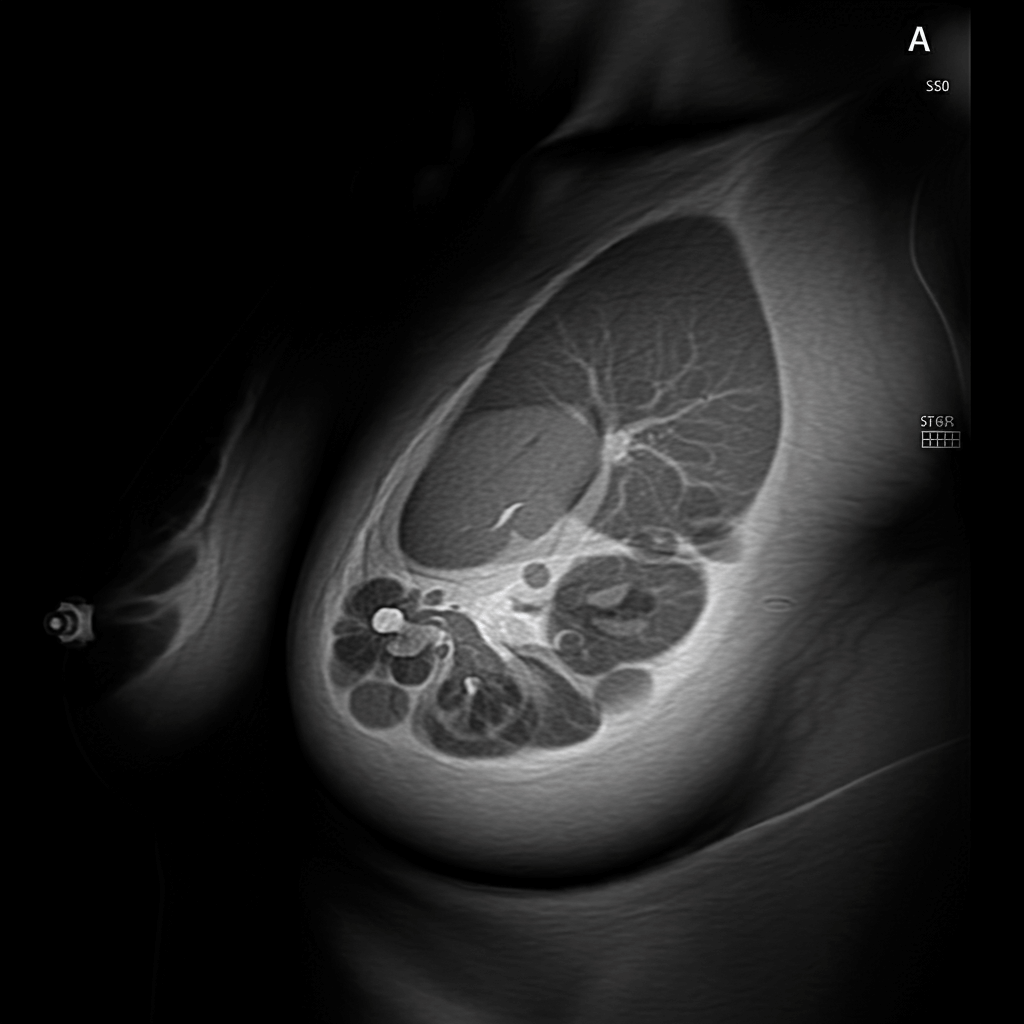

유방암

- 원인 및 특징: 여성호르몬, 가족력, 고지방 식단 등이 영향을 미칩니다. 30대 초반부터 발병률이 서서히 증가하며 조기 발견이 중요합니다.

- 검진 방법: 유방 초음파와 임상 진찰로 초기 징후를 확인할 수 있습니다.

- 예방: 자가진단을 생활화하고, 규칙적인 운동과 저지방 식단을 유지하세요.